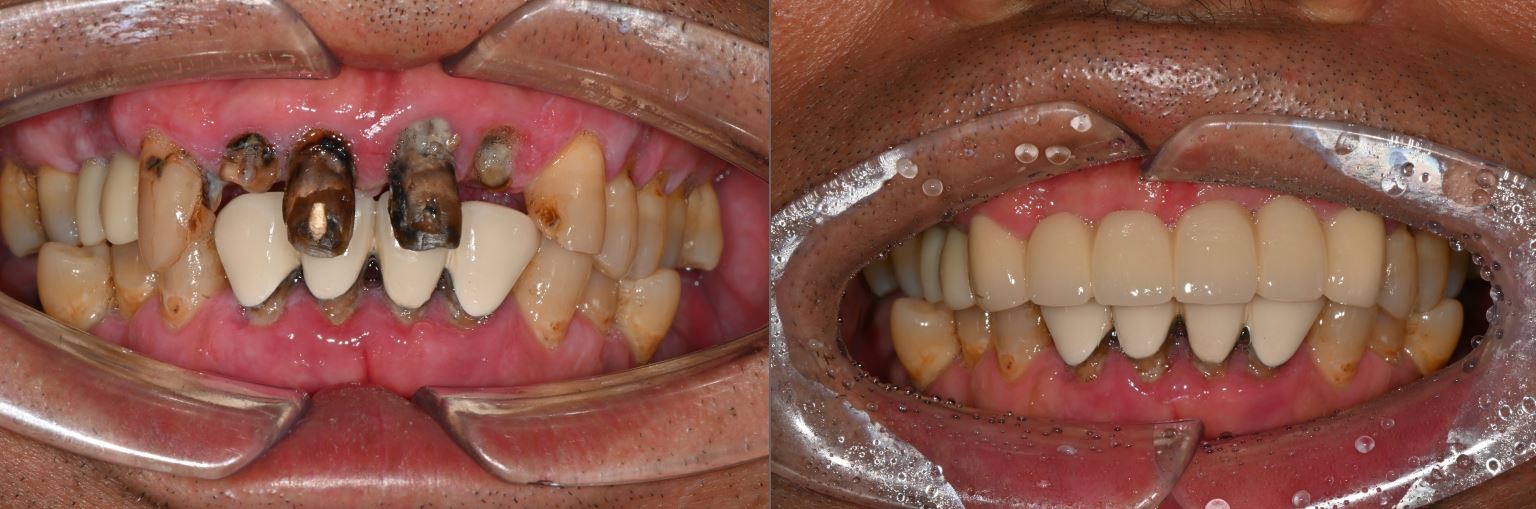

치료전후사진